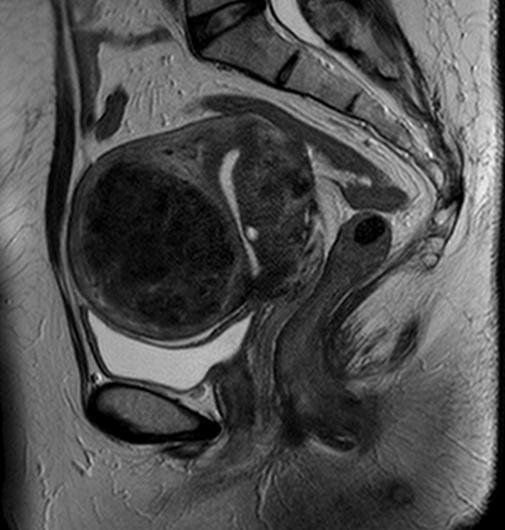

子宮や卵巣、前立腺など骨盤領域

骨盤部MRI 女性

MRIの方が優れています。

男性の前立腺、女性の骨盤部検査の第一選択肢はMRI検査です。

MRIは濃度分解能に優れており、CTでは困難な正常解剖の把握や腫瘍(前立腺・膀胱・子宮・卵巣・直腸など)、炎症、リンパ節病変などの疾患の鑑別が可能で、腹部の動きの少ない骨盤部の検査には適しています。